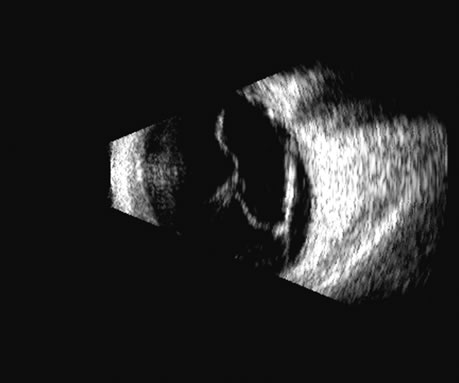

The retina is a highly reflective surface (specular reflector) and can be seen to always maintain its connection to the optic nerve, even when drawn into an organized detachment. It may not be attached at the ora serrata in giant tears, but otherwise it generally maintains the two “landmark” attachments of optic nerve and ora serrata (Fig. 13), which can aid in differentiating the retina from the PLM of the retracted vitreous and from the choroid, in which the detachment may extend anterior to the ora and rarely extend back behind the vortex veins to the nerve (Fig. 14).14

Fig. 14. A B-scan of an eye with “kissing” choroidal detachments. The smooth convex outline from the ciliary body back to the near periphery of the posterior pole can be seen. The choroidal space, though filled with blood, may often appear anechoic due to the recent, “fresh” nature of the hemorrhage.